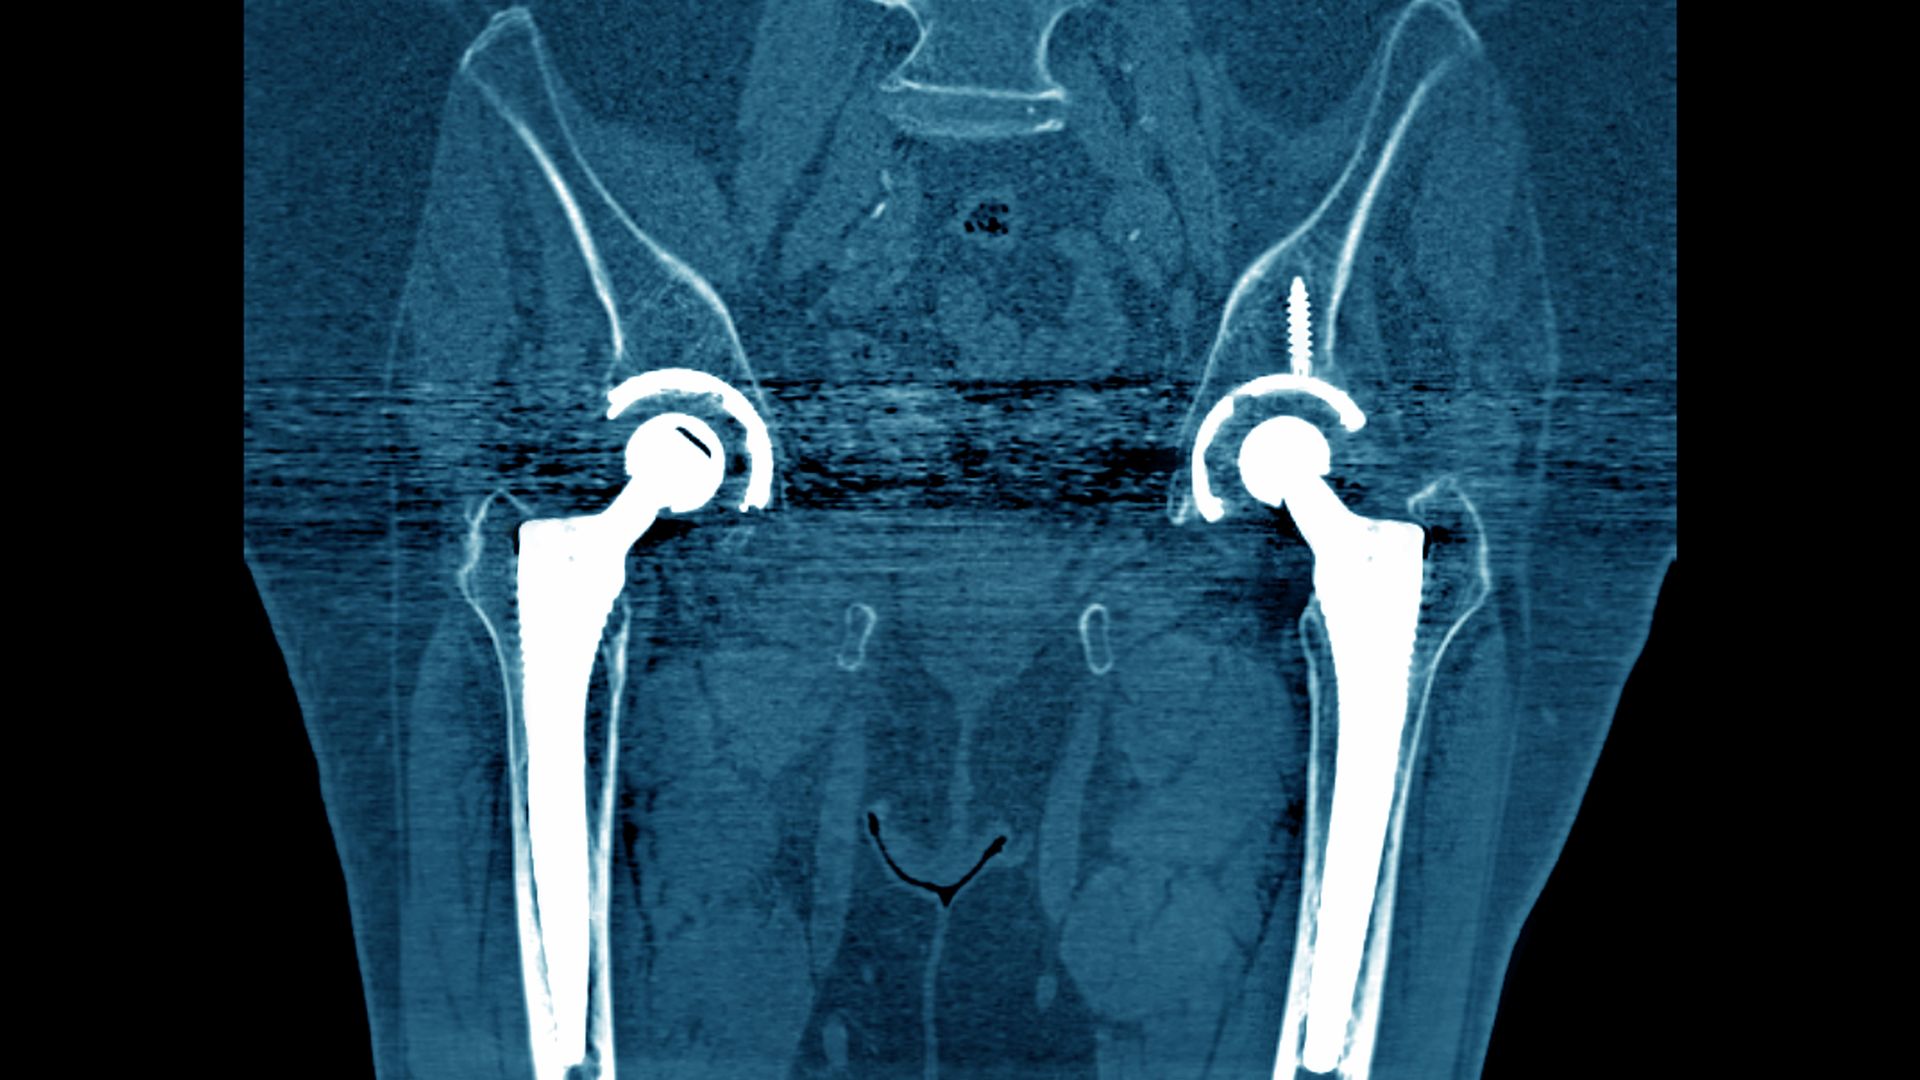

A CT scan of hip implants. Photo: BSIP/UIG via Getty Images